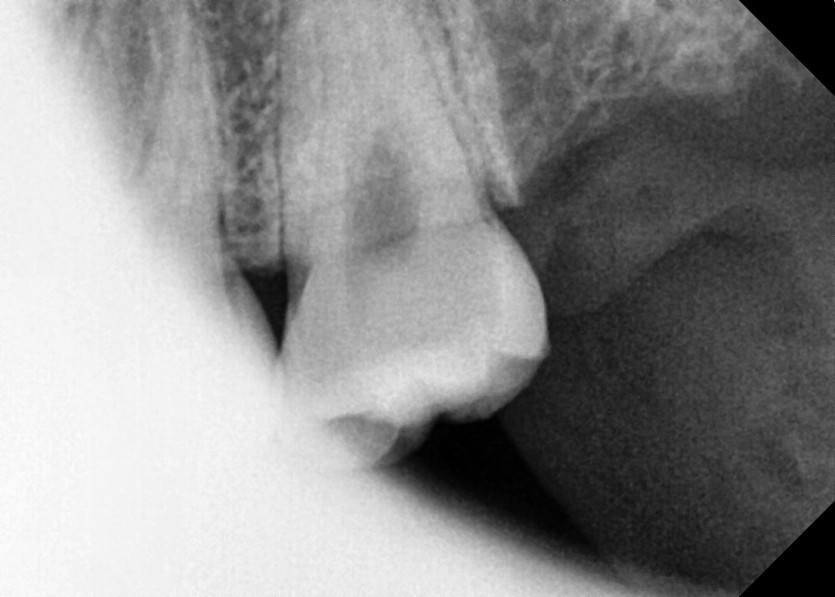

#18,28,38,48 사랑니 발치

구강 외과 전문의가 당일 발치했습니다.